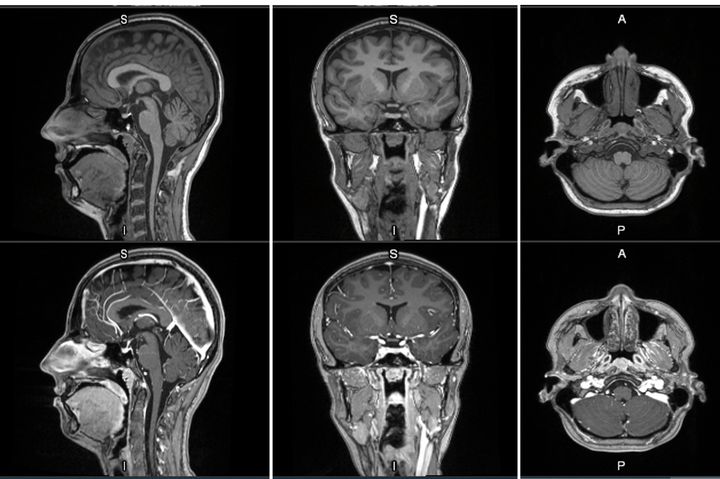

First-in-human contrast enhanced MRI images with GE HealthCare's mangaciclanol

MRI contrast agents enhance the visualization of abnormal structures or lesions during imaging procedures and help clinicians better distinguish between healthy and diseased tissue. Mangaciclanol is intended for general-purpose MR imaging and demonstrates comparable relaxivity (the ability to enhance signal intensity) to market-leading gadolinium-based agent, gadobutrol, with early clinical images suggesting similar diagnostic capability. Unlike gadolinium, which is a rare-earth metal, manganese is present in our food, and is an endogenous element, naturally occurring and autoregulated in the body. The macrocyclic ‘cage-like’ structure of mangaciclanol lessens the possibility of retention.